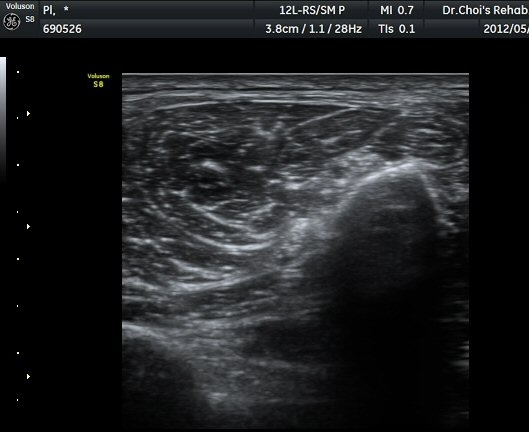

ŽÃËÀÚ¸¦ ´õ ¾Æ·¡·Î À̵¿ÇÏ´Ï Ãµºñ°ñ½Å°æÀÌ Àú¿¡ÄÚ µÕ±Ù µ¢¾î¸®·Î °üÂûµÇ´Ù°¡ ´Ù½Ã Á¤»óÀûÀÎ ¸ð½ÀÀ¸·Î °üÂûµÈ´Ù(±×¸² 7, 8).

µ¢¾î¸® Á¾´Ü¸é°Ë»ç¿¡¼­ µ¢¾î¸®ÀÇ ±ÙÀ§ºÎ°¡ ½Å°æ°ú ¿¬°áµÇ¾î ÀÖÀ½À» °üÂûÇÒ ¼ö ÀÖ´Ù(±×¸² 9).